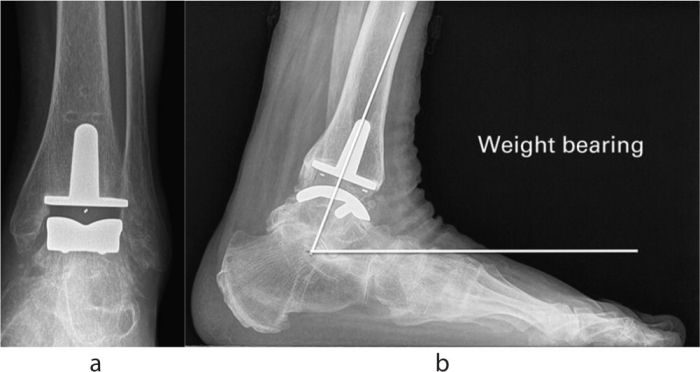

Artroplastia total de tobillo

Presentamos los resultados a medio plazo de una serie consecutiva de 118 artroplastias totales de tobillo (TAA) Zenith de un único centro que no fue diseñador.

Nuestros resultados muestran que las tasas de supervivencia de Zenith son comparables con las de la literatura para otros implantes y en el National Joint Registry (NJR). La satisfacción general del paciente fue alta, al igual que los resultados funcionales. Sin embargo, los datos destacan las posibles complicaciones asociadas con esta cirugía. Los autores creen que estas cifras apoyan la artroplastia de tobillo como una opción en el tratamiento de la artritis de tobillo.